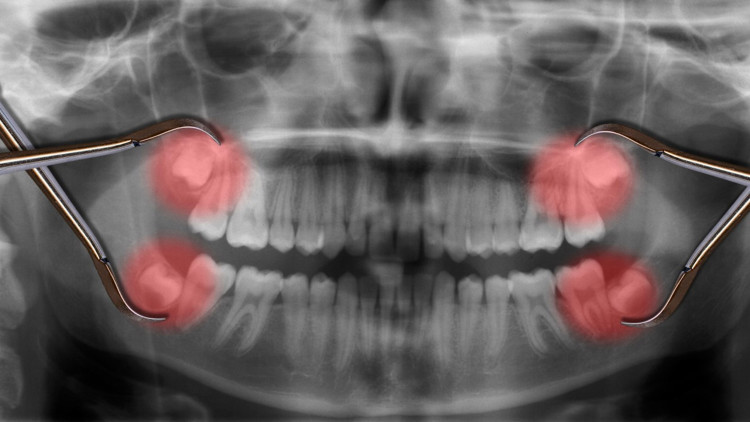

Yirmi yaş dişleri, çenenin iki tarafında en sonda bulunan üçüncü büyük azı dişlerine denir. Genellikle 16 ila 20 yaş arasında çıktığı için bunlara akıl dişi de denir. En son çıkan kalıcı dişler olduğu için, ağzınızda yirmilik dişler için yeterli boşluk olmayabilir. Bu da yirmi yaş dişlerinin dişeti dokusunun veya kemiğin altında veya başka bir dişin yanında gömülü kalmasına yol açabilir.

Diş Hekimi Dr. Onur Öztürk, yirmi yaş dişlerinin çene kemiğinin en arkasında yer alan dişler olduğunu ancak çeşitli nedenlerle bu dişlerin normal çıkışlarını tamamlayamadıklarını ifade etti:

“Çene kemiğinde en arkada yer alan yirmi yaş dişleri çıkamadığı zaman adı üzerinde 'gömülü' kalıyor, bu durumda üstünde bir miktar kemik engeli de olunca, buradan serbestleştirerek alınması gereken yirmilik dişler çoğunlukla operasyon ile çekilebiliyor.”

Öztürk, yirmi yaş dişlerimizin, atalarımız bugünkü gibi işlenmiş gıdalarla beslenmediklerinden dolayı, çiğ et ve sebzeleri parçalayabilmek için kafatasımızda yer etmiş olan çiğneyici dişler olduğunu, günümüzdeki modern beslenme modelinde bu dişlerin normal bir çene fonksiyonu için gerekliliğinin kalmadığını belirtti. Bununla beraber Öztürk, küçülen kafatasında yer bulmakta zorlanan yirmi yaş dişlerinin gömülü kalabileceğini ya da çıkmak için yer bulamayınca enfeksiyon gibi sorunlara yol açabileceğini ve şiddetli ağrılara neden olabileceğini söyledi.